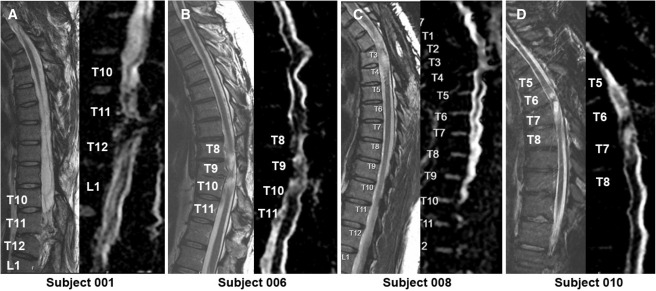

每位受試者接受了每個注射點含有2×105個神經干細胞,通過定制的立體定向設備,雙側注入損傷部位周圍的剩余組織及下方約一個節段的內側白質區,整個過程由術中熒光透視成像指導完成。

臨床結果:

1.神經系統反應概覽:按ISNCSCI隨訪,2名受試者(001、010)在移植后出現了明顯的神經學改善:001在移植后2年曾上升兩個節段,5年回落至上升1個節段;010則在整個5年隨訪期間保持了穩定的神經功能提升。

4.影像學評估:術后MRI顯示所有患者存在不同程度的局灶性脊髓軟化,但未見新的并發影像學征象(如水腫、增強或積液);DTI提示脊髓束外觀穩定,未見廣泛重塑或纖維束改善。